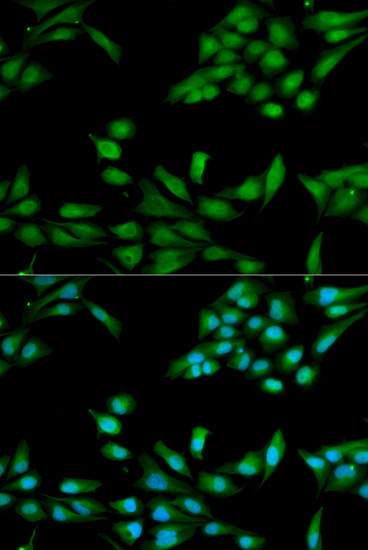

Immunofluorescence analysis of HeLa cell using MSH2 antibody. Blue: DAPI for nuclear staining.

Immunofluorescence analysis of U2OS cell using MSH2 antibody. Green:BRCA1 used for DNA damage marker. Blue: DAPI for nuclear staining. Cells were treated by UV-A laser.